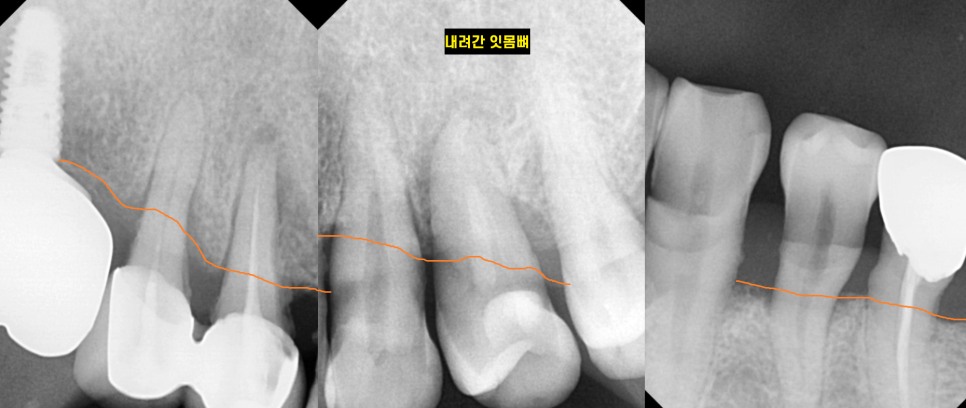

최대한 치아를 많이 살리고 싶어서

치아 1개씩 사진을 찍어

평가해보았습니다.

240425